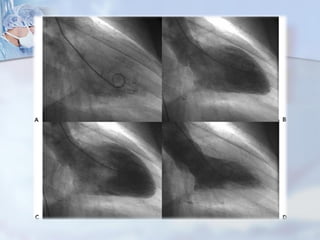

Ventriculografía Izquierda

Segmentos VI

OAI

OAD

Hipoquinesia

Acinesia

Contracción

paredes VI